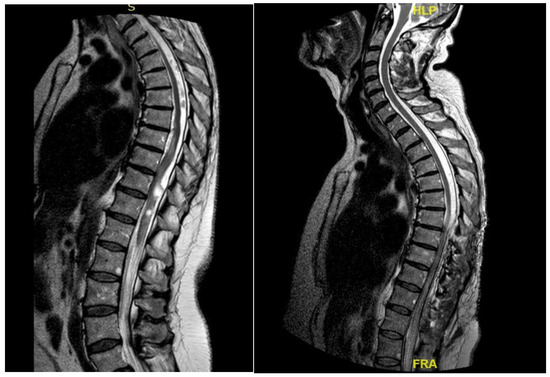

3.4.2. Case 2

| Patient | 1 | 2 | 3 | 4 | 5 |

|---|---|---|---|---|---|

| Age | 46 | 48 | 62 | 43 | 68 |

| Gender | M | M | M | F | F |

| Level | T12–L2 | C5–C6 | T7–T10 | T8–T9 | T8–T11 |

| Location | Intramedullary | Intradural | Intradural–Extradural | Intramedullary | Intradural |

| Primary/secondary | Secondary | Secondary | Secondary | Secondary | Secondary |

| Numbness | Yes | No | Yes | Yes | Yes |

| Gait disturbances/ataxia | No | Yes | No | Yes | Yes |

| Lumbar pain | No | No | Yes | Yes | No |

| Urinary–bowel dysfunction | Yes | No | Yes | No | No |

| Limb weakness | Yes | Yes | No | No | No |

| Paraplegia | No | No | Yes | No | No |

| Sexual disfunction | Yes | No | No | No | No |

| Surgical treatment | lysis of adherences and syrinx cavity opening | resection of the cystic formation and adhesiolysis | resection of the cystic formation and adhesiolysis | resection of the cystic formation and adhesiolysis | resection of the cystic formation and adhesiolysis |

| Complications | CSF fistula | infection | None | CSF fistula | None |

| KPS pre-op (%) | 70 | 50 | 70 | 80 | 90 |

| KPS post-op (%) | 80 | 50 | 60 | 90 | 80 |

| ASIA score pre-op | C | B | B | C | D |

| ASIA score post-op | D | B | C | C | D |

| Follow-up (years) | 2 | 2 | 2 | 3 | 1 |